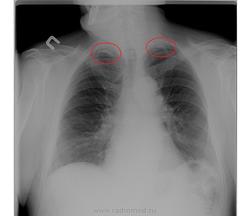

2-ой случай: обызвествлена апикальная плевра, кальцинаты.Это не от возраста, а посттуберкулезные изменения.

Что-то неубедительно с газом, если есть сомнения сделайте ОБП на левом боку, снимаем только правую сторону. Случай 2. Думаю, что возрастное обызвествление плевры. Опять же порекомендую прицельно верхушки.

По первому - газа нет. По второму - мелкие тени обызвествления в верхушках.

Не доводилось встречать апикальный фиброз с двух сторон.Может,конечно быть,но склоняюсь,что это в рёбрах.

Я встречала. Только это уж не фиброз, кальций тут.